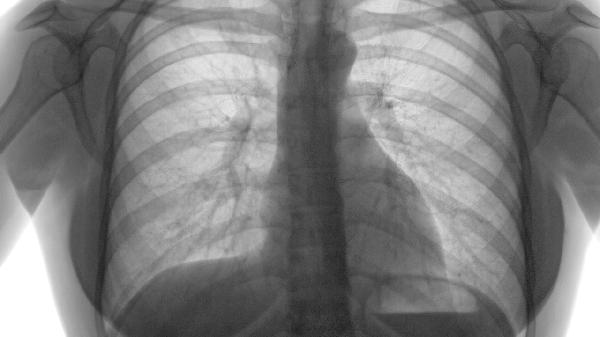

臌症丸由皂矾、甘遂、木香等成分组成,具有利水消肿的功效,其适应证明确指向肝硬化、血吸虫病等引起的腹水。肺气肿则是肺泡壁破坏导致的气体交换功能障碍,临床表现为呼吸困难、咳嗽等,需通过支气管扩张剂、糖皮质激素等药物改善通气功能。两者治疗目标和药物作用机制无直接关联。

极少数情况下,若肺气肿患者合并严重右心衰竭引发胸腔积液,可能需短期配合利尿剂缓解症状。但臌症丸并非临床常规选择,且其含峻下逐水成分,可能加重电解质紊乱风险。肺气肿急性发作时应优先使用沙丁胺醇气雾剂、氨茶碱片等呼吸科专用药物。